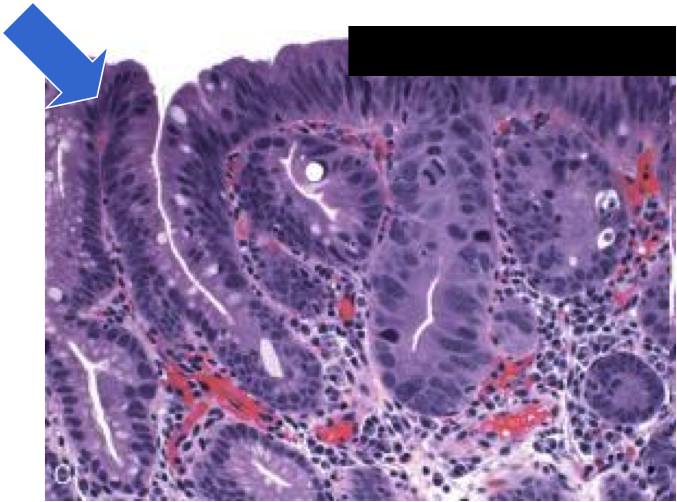

Barrett’s esophagus: columnar metaplasia (intestinal metaplasia)+goblet cells

dysplasia in barrett’s

sequence of adenocarcinoma is metaplasia–>dysplasia–>carcinoma